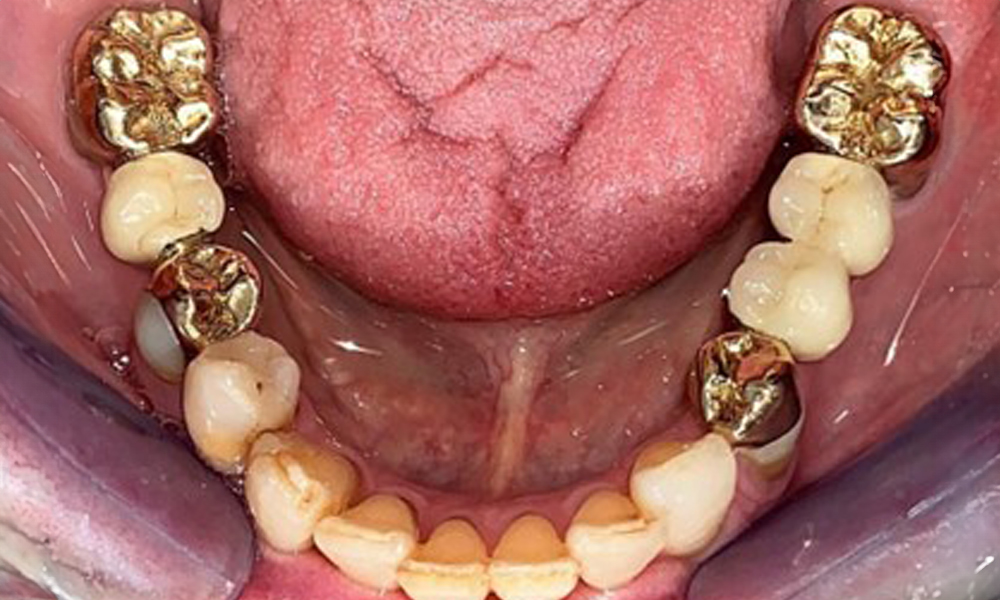

Occlusal view of the mandible.

Fig. 4: Occlusal view of the mandible.

The dental findings are as follows: Combined removable implant and tooth-supported telescopic prostheses on implants 15, 13, 21, 23, 24, 25 and tooth 11 (Fig. 1, Fig. 2, Fig. 3). The patient was fitted with a fixed mandibular denture. Adequate bridges were present over 37 to 34 and 45 to 47 (Fig. 4), the crown margins were intact and there were no active caries. A composite filling with a marginal gap was present on tooth 43. There was mandibular gingival recession, exposing 1 to 3 mm of root surface. This also applies to 11.

The radiological findings show partially edentulous dentition with maxillary implants for teeth 15, 13, 21, 23, 24, 25 and a telescopic crown on tooth 11. Adequate mandibular bridges spanning 37 to 34 and 45 to 47 are present. 48 is impacted. There are suspected secondary caries distally on 43 and mesially on 44. 44 is restored with a non-radiopaque cavity lining. There is generalised horizontal bone loss of approx. 10% to 30% and localised vertical bone loss affecting teeth 22 and 42 (Fig. 5).

Panoramic X-ray image. The patient has a full set of adult teeth with generalised bone loss of between 10% and 30%. There is radiological suspicion of secondary caries on 44 and 43.

Fig. 5: Panoramic X-ray image. The patient has a full set of adult teeth with generalised bone loss of between 10% and 30%. There is radiological suspicion of secondary caries on 44 and 43.